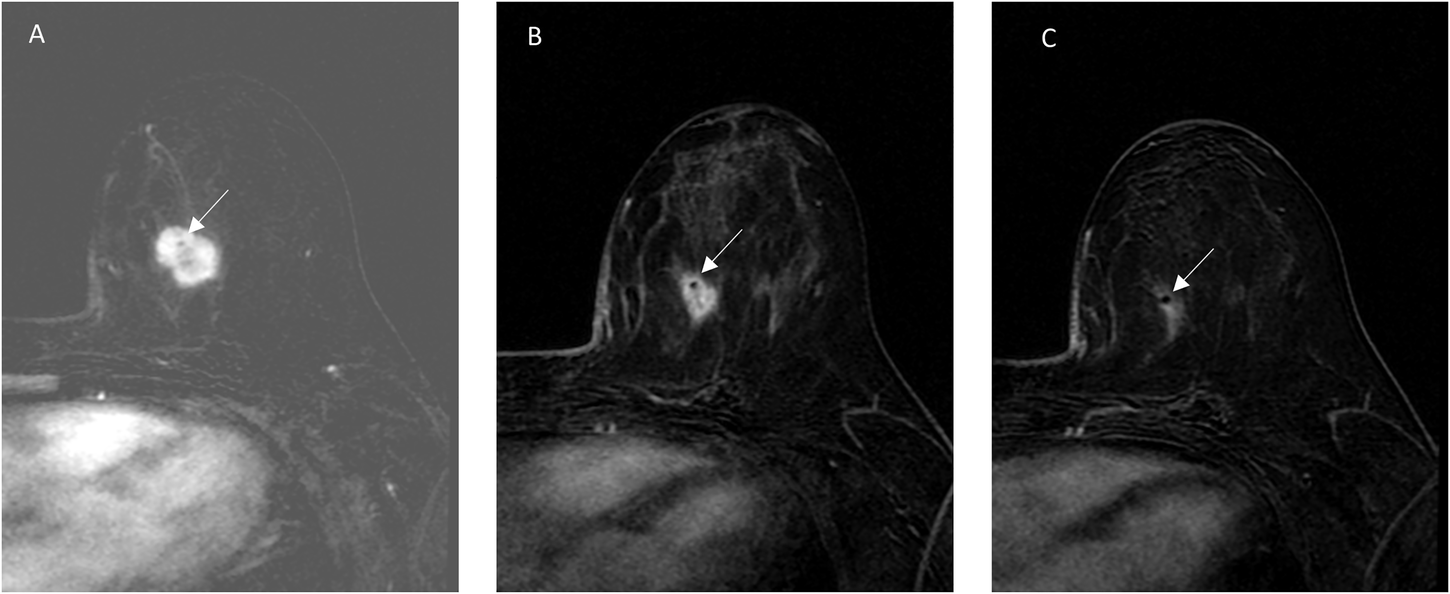

Fig. 2: A 44 year-old woman with TNBC undergoing NAST.

MRI at baseline (A), after two cycles (B), and four cycles (C) of AC shows an oval, heterogeneously enhancing mass with associated clip marker (arrows). MRI shows concentric shrinkage and tumor volume reduction of 83% after two cycles, and 96% after four cycles. Pathology after the completion of NAST confirmed pathologic complete response.